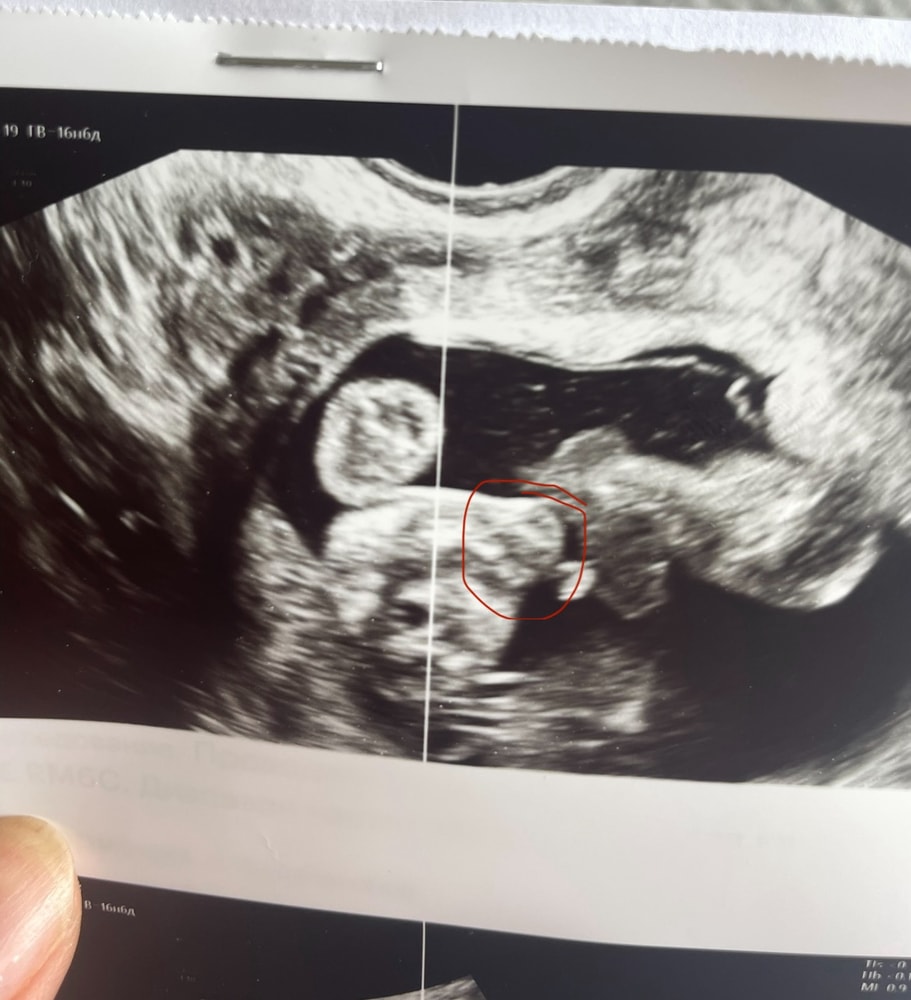

Маргарита , Где я обвела кружочком, врач сказала, что это похоже на мошонку Изображение

Светлана , это вообще какие части тела зафотали? Реально не понятно и это точно не мошонка

03.05.2025